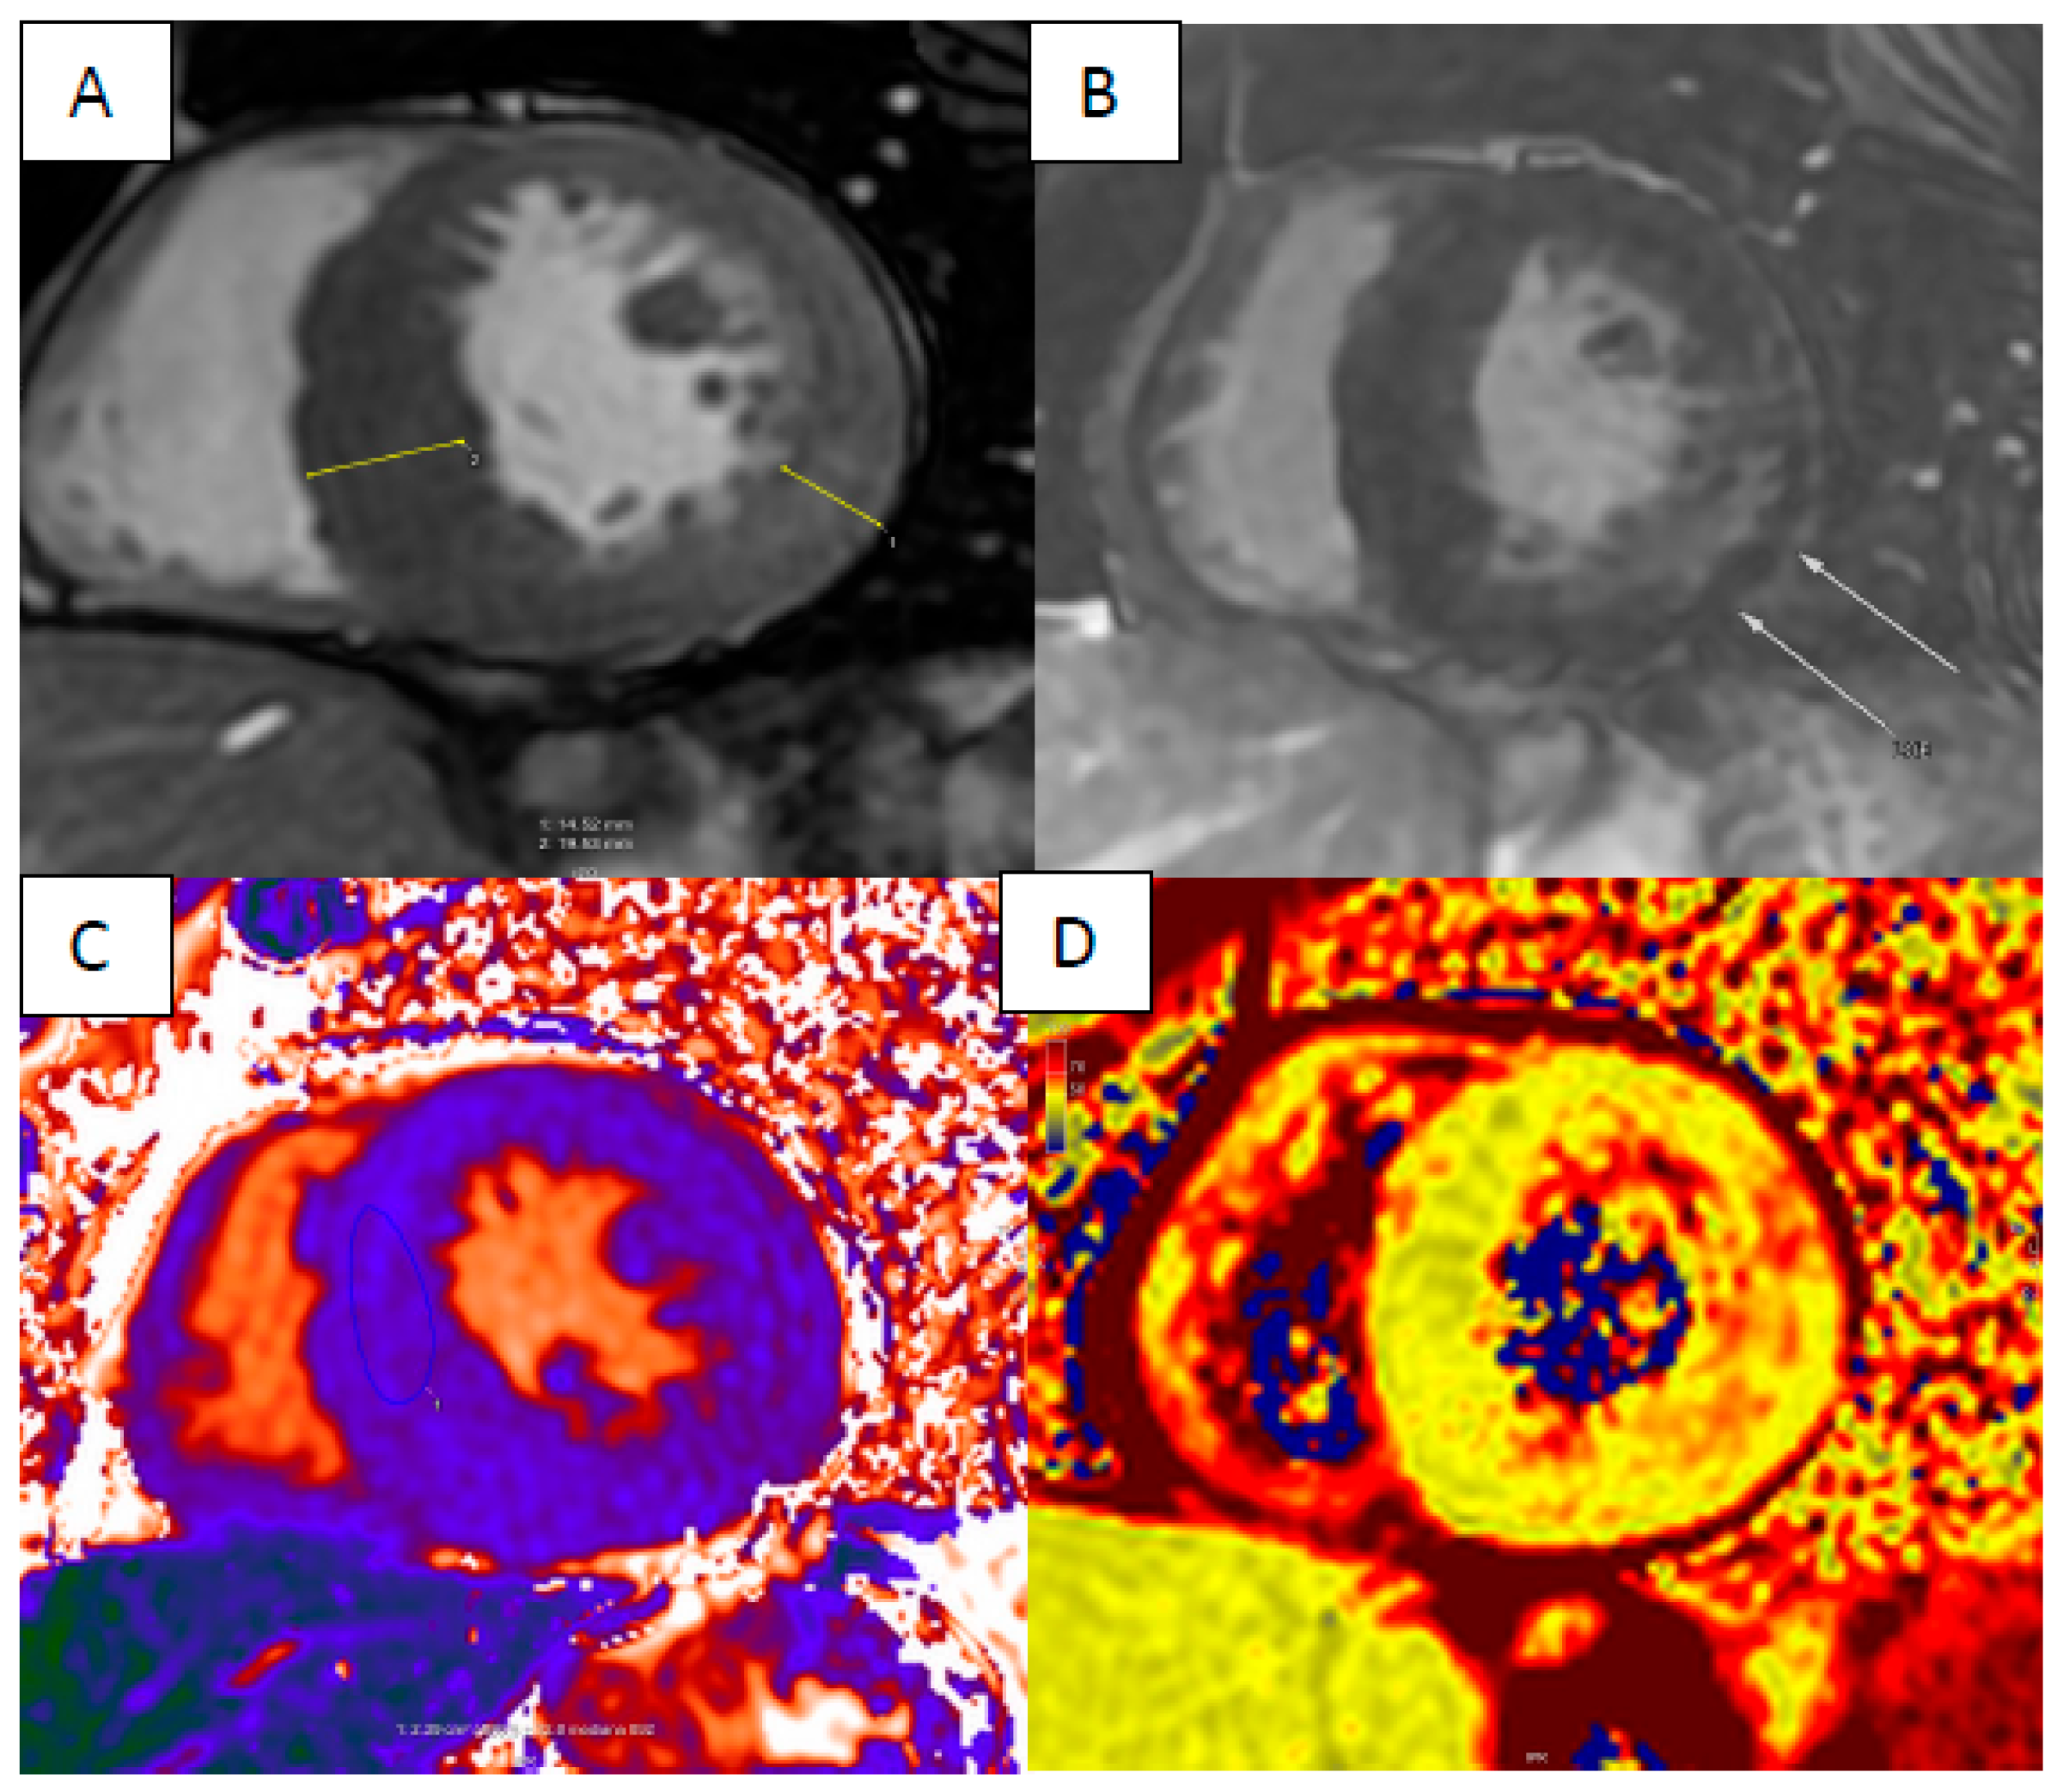

6. Myocardial Iron Overload